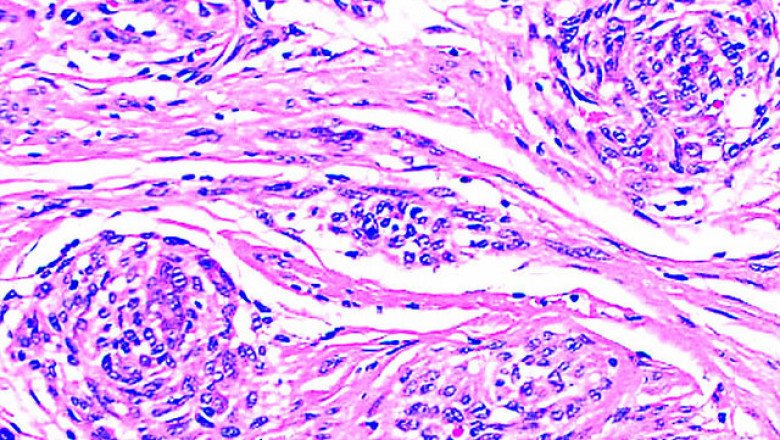

Plexiform Neurofibromas Treatment Market